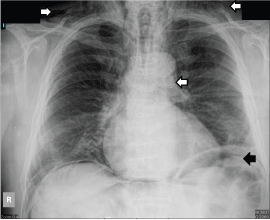

A 68-year-old man live with a prosthetic aortic valve and treated with a vitamin K antagonist was admitted to our department for control colonoscopy 10 years after sigmoid resection due to previous adenocarcinoma. Before the procedure, coumarin was replaced by low-molecular weight heparin. After complete colonic preparation the colon was viewed up to the ileocoecal junction. During colonoscopy a 3 cm long polyp was resected by Endoscopic Mucosa Resection (EMR) in the ascending colon (Figure 1). On the base of this area, a deeper mucosal hiatus was clipped. Furthermore, an approximately 6 cm long sessile polypus was detected in the sigmoid colon, which was extracted in pieces. No complications were detected through the examination. Two hours after colonoscopy the patient complained of a swollen neck, with pain in his neck, as well as mild shortness of breath without any abdominal pain. On physical examination crepitus was palpated in the neck and upper thorax of the patient, clearly signs of subcutaneous emphysema. Breathing sounds were normal. On physical examination the abdomen was palpable, soft, tenderness was not detected and normal bowel sounds were heard. The patient was hemodynamically stable, conscious, and afebrile. Chest and abdominal x-rays showed 26 mm wide left subdiaphragmatic air. Air was also detected in the mediastinum continuing to the aorta, as well as cervical subcutaneous emphysema (Figure 2). Initial laboratory parameters were in the normal range, C-reactive protein was 3.4 mg/l, and white blood cell count was 7020/μl. As perforation was suspected, 400 mg b.i.d. ciprofloxacin and 500 mg t.i.d. metronidazole combined intravenous antibiotic therapy was started immediately. The patient was transferred to the surgical department for further observation. Because symptoms of peritonitis were not present and inflammatory laboratory tests remained in a normal range, conservative therapy i.e. combined broad spectrum antibiotics and a fasting regimen was continued. On control x-rays, the amount of air decreased everywhere. On the 3rd hospital day, hematochezia causing anaemia was detected. Control colonoscopy detected no active bleeding signs and no signs of perforation. In the ascending colon, clear base of mucosectomy with clips were seen. A 3 cm large remnant polyp was seen in the sigmoid colon, the base of the previous sigmoid polypectomy was fixed and could not be resected with colonoscopy. After transfusion the patient was stable. Histology of the sigmoid tumor revealed adenoma with high grade dysplasia with focal carcinoma that was limited to the mucosal layer. Because of this finding, the patient went through open sigmoid resection one month later. During surgery a retroperitoneal inflammatory mass was detected next to the sigmoid colon. The excised specimen was histologically diagnosed as villous adenoma with high grade dysplasia. No residual tissue was identified at the resection margins. He was discharged fully recovered. Oncological follow-up of the patient will be continued.

Figure 2: Chest x-ray showing subcutaneous emphysema, subdiaphragmatic air and pneumomediastinum (see arrows). View Figure 2